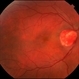

- Imaging device

-

Fundus camera

Optos Fundus Camera - Description

- 65-year-old-male with curtain/veil over vision for two days.